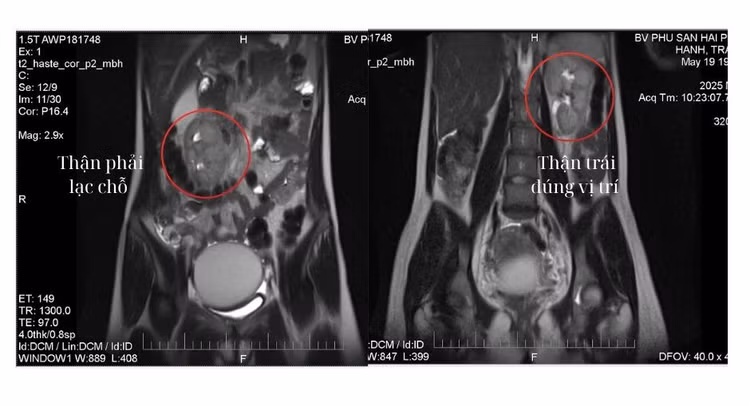

Qua thăm khám lâm sàng kết hợp siêu âm và chụp cộng hưởng từ (MRI), phát hiện khối u lạc nội mạc buồng trứng trái kích thước lớn (d=66 x 75 x 86 mm).

Khối u lạc nội mạc buồng trứng trên nền thận lạc chỗ - Ảnh BVCC

Tuy nhiên, ca bệnh lại đặc biệt phức tạp do bệnh nhân đồng thời mắc dị tật bẩm sinh – thận phải lạc chỗ (thận phải nằm ở thành bụng trước bên phải) làm tăng nguy cơ tổn thương thận và niệu quản trong quá trình phẫu thuật.